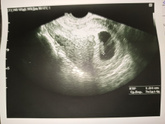

Вчера была на УЗИ. Беременность маточная прогрессирующая, соответствует сроку 7 недель. Сердцебиение есть 158 ударов в минуту, копчико теменной размер 10,4 мм. Развивается хорошо!